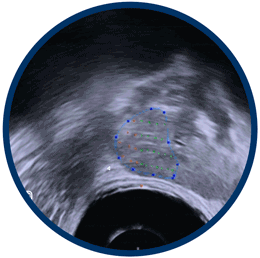

We map the cancer using real-time MRI fusion imaging.

1.7mm targeting accuracy guided by MRI fusion.